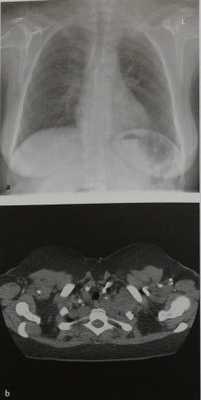

Нейрофиброма у женщины 38 лет.

На обзорной рентгенограмме грудной клетки верхний отдел средостения расширен в обе стороны, но больше слева в области верхней апертуры грудной клетки. Еще одна опухоль, имеющая мягкотканную плотность, расположена латеральнее вдоль ребер в левом верхнем легочном поле. Имеется также локальное затемнение в области корня правого легкого.